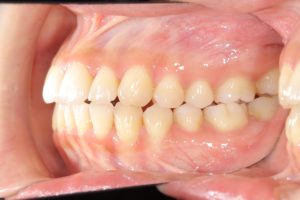

【スプリント治療後】

歯並びは変わっていませんが、顎の位置が正常に安定したことで

噛み合わせの位置が変化していることが分かります。

正しい位置で咬めるようになったためインビザラインに移行します。

【インビザラインにて動的治療スタート】

約2年6ヵ月、インビザラインによる非抜歯での動的治療。

【動的治療終了時】

スプリントの期間も合わせると約3年で歯並び、噛み合わせともにしっかり整いました。

この状態がキープできるようリテーナー(保定装置)に切り替え、保定期間に入ります。